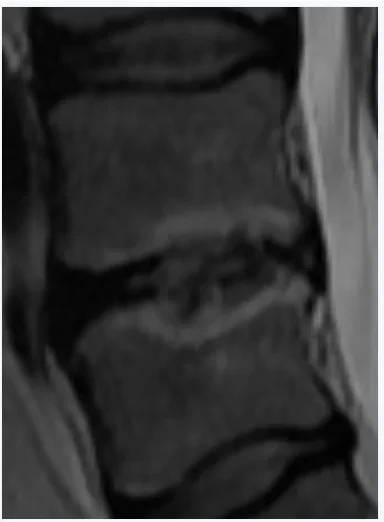

Mä pistän tohon pari croppausta noista magneettikuvista, jos ette oo nähny miltä "diskusdegeneraatio" näyttää. Ja vielä voimakasasteinen sellainen. Ei tarvi olla tosiaan radiologian erikoislääkäri nähdäkseen noista että vikaa on kun vertaa tota yhtä kohtaa muihin välilevyihin.

• MRIZoomattu.webp

MRIZoomattu.webp

6,5 KB · Katsottu: 737